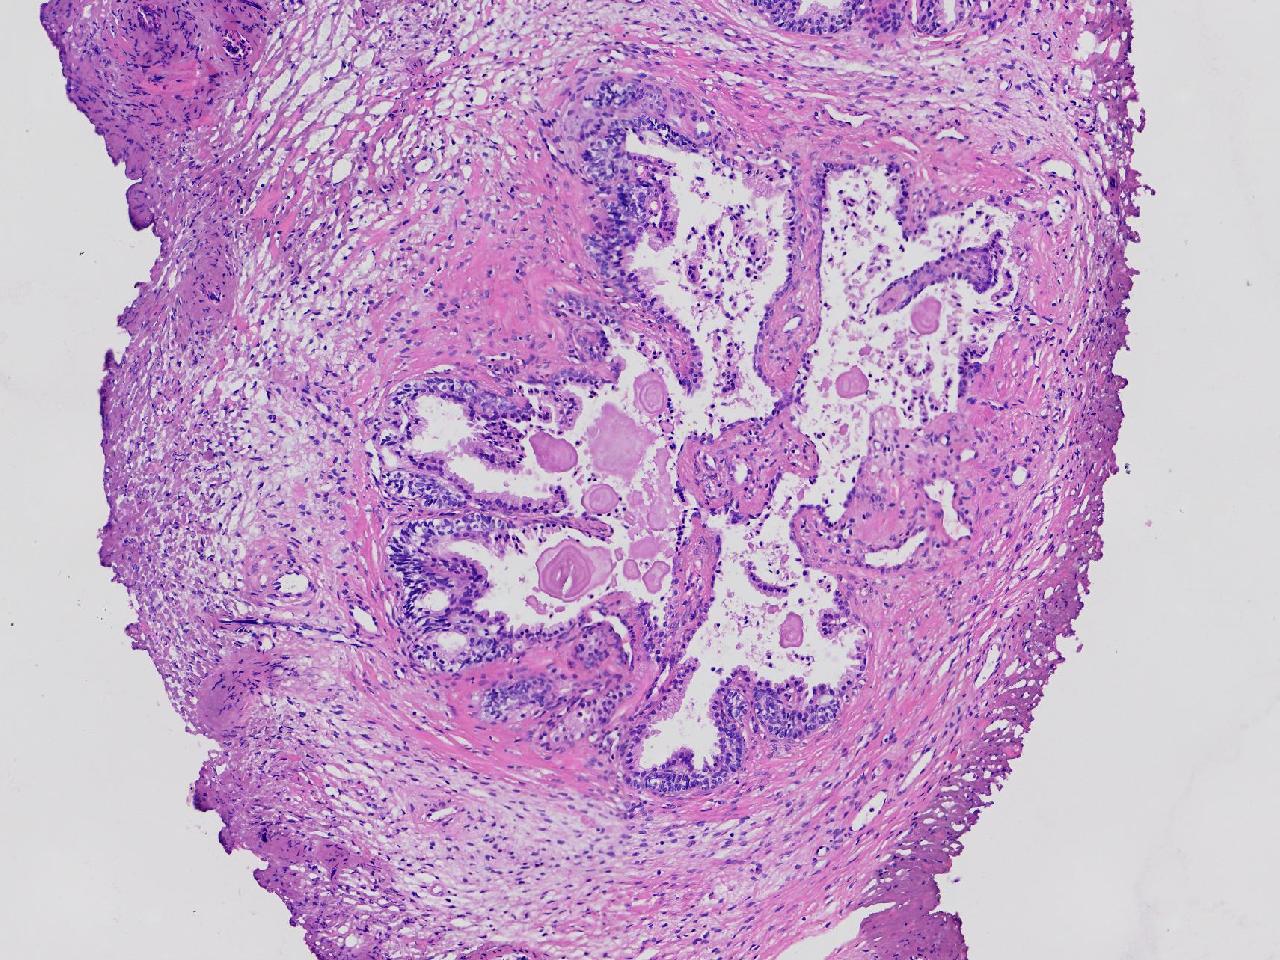

这些腺体有问题吗?

男,77岁,排尿困难2年,尿潴留3天。

标本名称

电切前列腺组织

条索状软组织多块,5X5X4厘米。